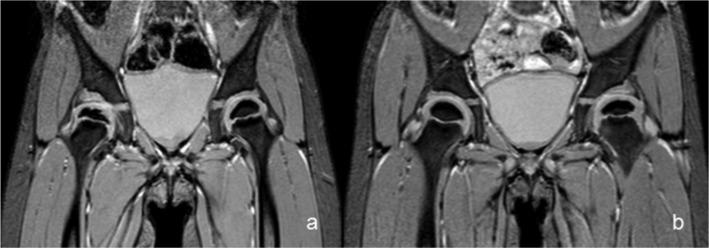

A total of 55 patients (59 hips) with late-detected DDH underwent MRI after CR. Hip abduction angle and hip joint distance were measured on postoperative MRI transverse sections. The acetabular index and centre-edge angle were measured on plain radiographs at the last follow-up. The presence of AVN according to Kalamchi and McEwen's classification was assessed. We retrospectively analyzed the associations among abduction angles, hip joint distances, radiographic parameters, AVN and final outcomes, exploring the relationship between hip joint abduction angle and AVN rate.

The mean age at the time of CR was 14.4 months SD 5.5 (6 to 28), and the mean follow-up was 26.2 months SD 8.1 (12.4 to 41.7). The mean hip abduction angle was 70.2° SD 7.2° (53° to 85°) on the dislocated side and 63.7° SD 8.8° (40° to 82°) on the normal side; the mean hip joint distance was 5.1 mm SD 1.9 (1.3 to 9.1) on the dislocated side and 2.2 mm SD 0.6 on the normal side (1.3 to 3.3). Eight of 59 hips (13.6%) developed AVN. Neither the amount of abduction nor hip joint distance increased the AVN rate (p = 0.97 and p = 0.65, respectively) or the dislocation rate (p = 0.38 and p = 0.14, respectively).